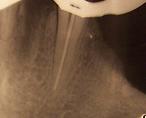

Esta es una fase muy importante que además condiciona las restantes y de la que depende en gran medida el éxito de la endodoncia. Consiste en medir la longitud exacta de cada conducto tomando como referencia alguna parte de la corona del diente. Clásicamente se hace por medio de una radiografía, habiendo introducido en el diente una lima endodoncia a modo de referencia. Hoy en día es muy importante contrastar esa medida de manera mucho más exacta con el uso de localizadores electrónicos de ápice.